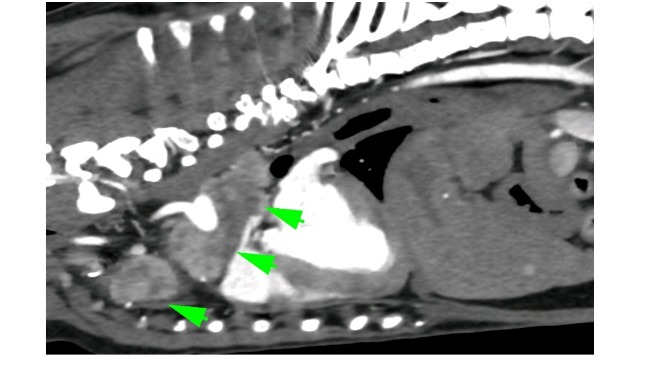

Od tego momentu zostało wykonane RTG, liczne USG, badania krwi, Echo serca...i w koncu TK z kontrastem, które niestety potwierdziło bardzo smutną dla mnie diagnozę...guz podstawy serca💔

Guz o średnicy 4,5 cm uciska mu aortę i tchawicę. Niestety są już także przerzuty w węzłach chłonnych śródpiersia.

Pomimo tak strasznej diagnozy, Keko jest w dobrej kondycji klinicznej, ma apetyt i uwielbia spacery, coprawda już w swoim własnym tempie, bo ma nadciśnienie płucne i zadyszkę, przez ucisk guza na tchawicę i płuca.